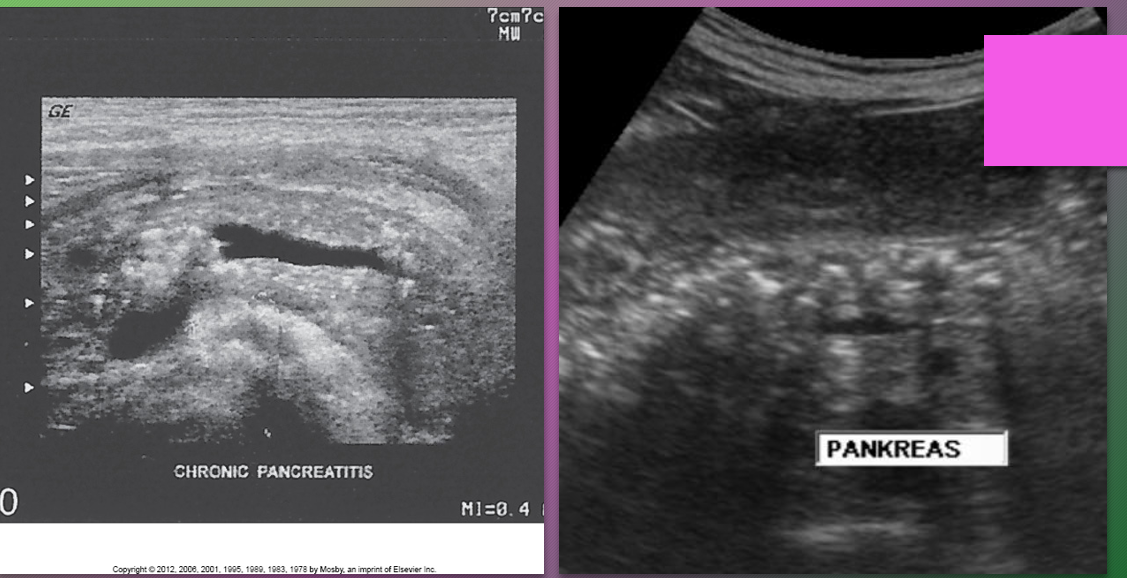

Chronic pancreatitis results from _____ attacks of ____ pancreatitis and causes continuous ______ of the pancreatic parenchyma

recurrent; acute; destruction

Sonographically, chronic pancreatitis may appear _____ or ______ with increased ______, size _____, ______ borders, and ______ duct

localized; diffuse; echogenicity; reduced; irregular; dilated

What is a classic finding of chronic pancreatits?

Calcification